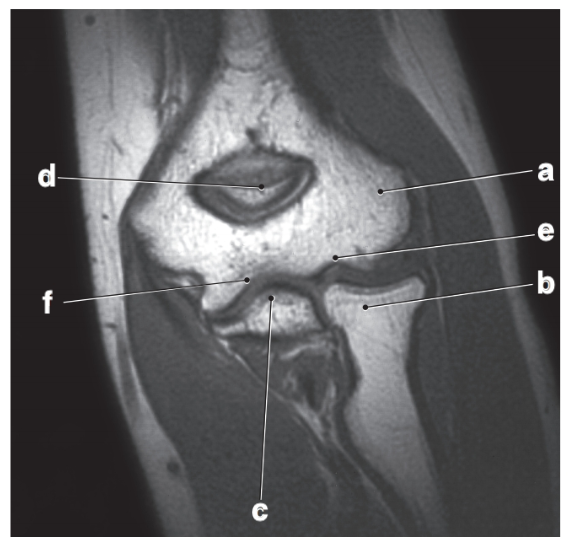

Medial meniscus

posterior cruciate ligament

Which letter is pointing to the posterior cruciate ligament?

e

b

medial collateral ligament

Which letter is pointing to the anterior cruciate ligament?

c